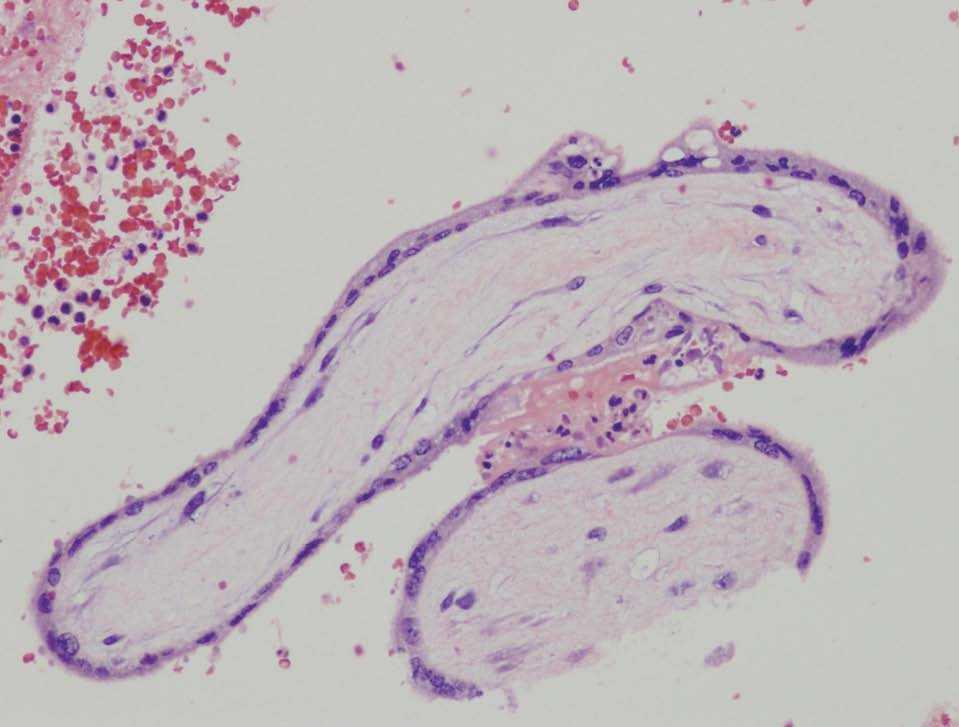

Figura 1. Vista a gran aumento de las vellosidades coriales dentro del coágulo de sangre en el omento extirpado.

Normalmente, las gestaciones en el epiplón se dividen en 2 grupos: primarias y secundarias. En las primarias, debe encontrarse evidencia histológica de neovascularización o crecimiento del trofoblasto en el tejido de soporte. En ausencia de esta evidencia histológica, todos los casos deberían considerarse secundarios7. En nuestro caso, el examen microscópico de la pieza mostró vellosidades coriónicas dentro de un coágulo de sangre y de tejido graso del epiplón (figs. 1 y 2), aunque no se pudo objetivar ningún tipo de invasión trofoblástica del tejido del omento. Esto podría explicarse por la gran hemorragia existente en el momento de la cirugía. Aunque nuestro caso podría ser encuadrado dentro de una gestación primaria en el epiplón según los criterios clínicos de Studdiford, el examen histológico no fue decisivo a la hora de determinar si se trata de un caso de gestación primaria o secundaria en el epiplón.